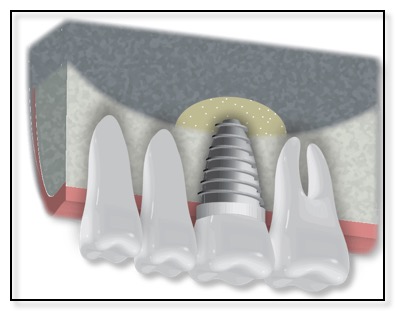

There are two basic types of bone grafting for dental implants. The most common one is after you have a tooth extracted, or if you lost a tooth awhile back. There could be insufficient bone support in such scenarios and thus a bone graft is needed. (See diagram above.) Dr. Tsai will numb the gum before making an incision to expose the area requiring the graft, or if the tooth was just extracted, then she will gently push the gum back to expose the existing bone. She will then place the graft, anchoring it in place if necessary, before covering it with a membrane and suturing the gum back in place. You will be given instructions on how to care for the bone graft site, and how to keep it clean. Bone grafts generally need to be left to heal for several months, although, if the amount of bone grafted was relatively small, it may be possible to place the implant at the same time.

Once the bone is heal, Dr. Tsai will place the implant, allow that to integrate with the bone, and then restore with an Abutment and Crown.

The other common type of bone graft for dental implants is a Ridge Augmentation, Ridge Enhancement, or Split Ridge. (See the diagram above.) Sometimes, when a patient has lost their tooth many months or years ago, the bone in that area has resorbed (the bone is lost). The remaining bone is too thin to support the dental implant. In such cases, Dr. Tsai would numb the area where the thin wall is, gently pull the gum tissue back, pack or place the bone graft in place, and suture the gum back into place. Sometimes Dr. Tsai will “split” the ridge and pack in the bone graft in order to thicken up the bone for the implant. This procedure typically takes 4-7 months to heal. Once the bone grafting has integrated or is healed, the dental implant can be placed.